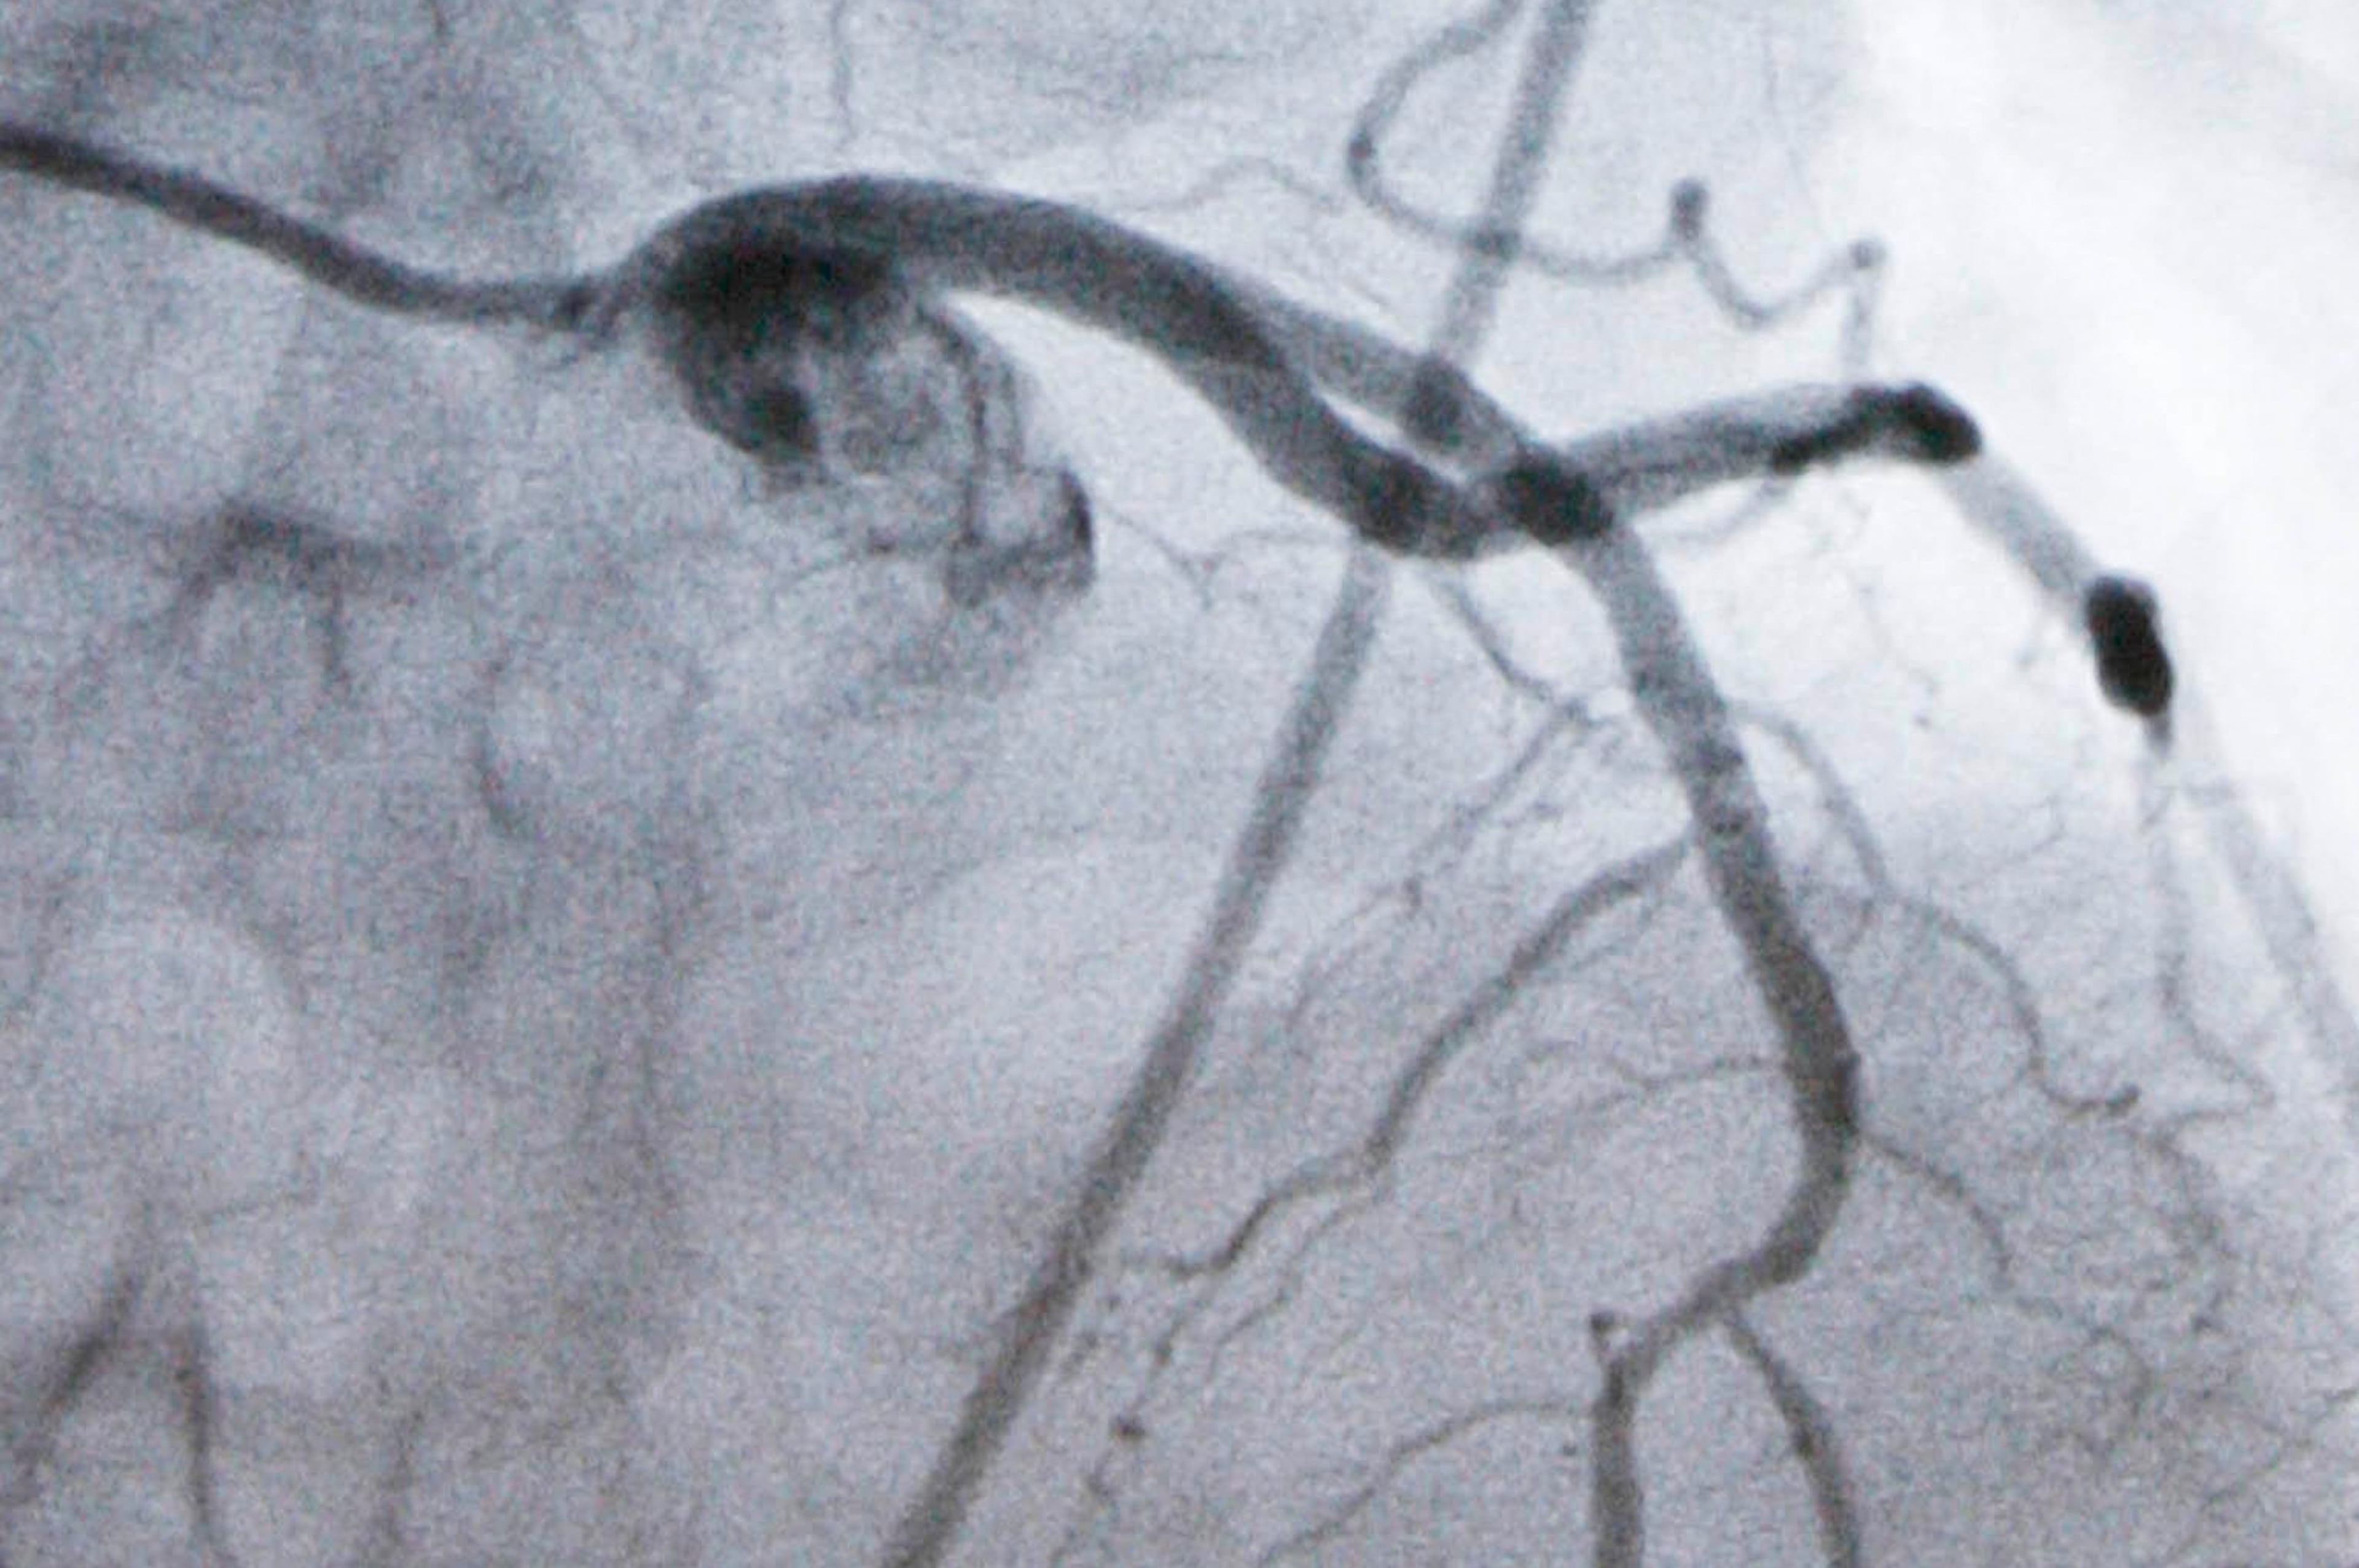

Pradilla told the AJC the new technique represents a paradigm shift because it routes a small tool via a small incision into the brain in order to reach and then remove blood clots resulting from the hemorrhage. Previously, the standard operation to remove blood clots in the brain entailed a conventional craniotomy — a large skin incision, removal of a section of skull and then the arduous process of reaching the actual blood clot. That process could entail suctioning out or transecting brain tissue, leaving open the potential for additional brain damage from the surgery itself.

During this latest trial, the team will take lessons learned treating hemorrhages in an area of the brain closer to the skull and apply them to stokes that occur in a deeper area of the brain known as the basal ganglia.

Hemorrhagic stroke occurs when a weakened vessel ruptures and bleeds into the surrounding brain. The buildup of blood inside the skull can crush brain tissue and cause damage.